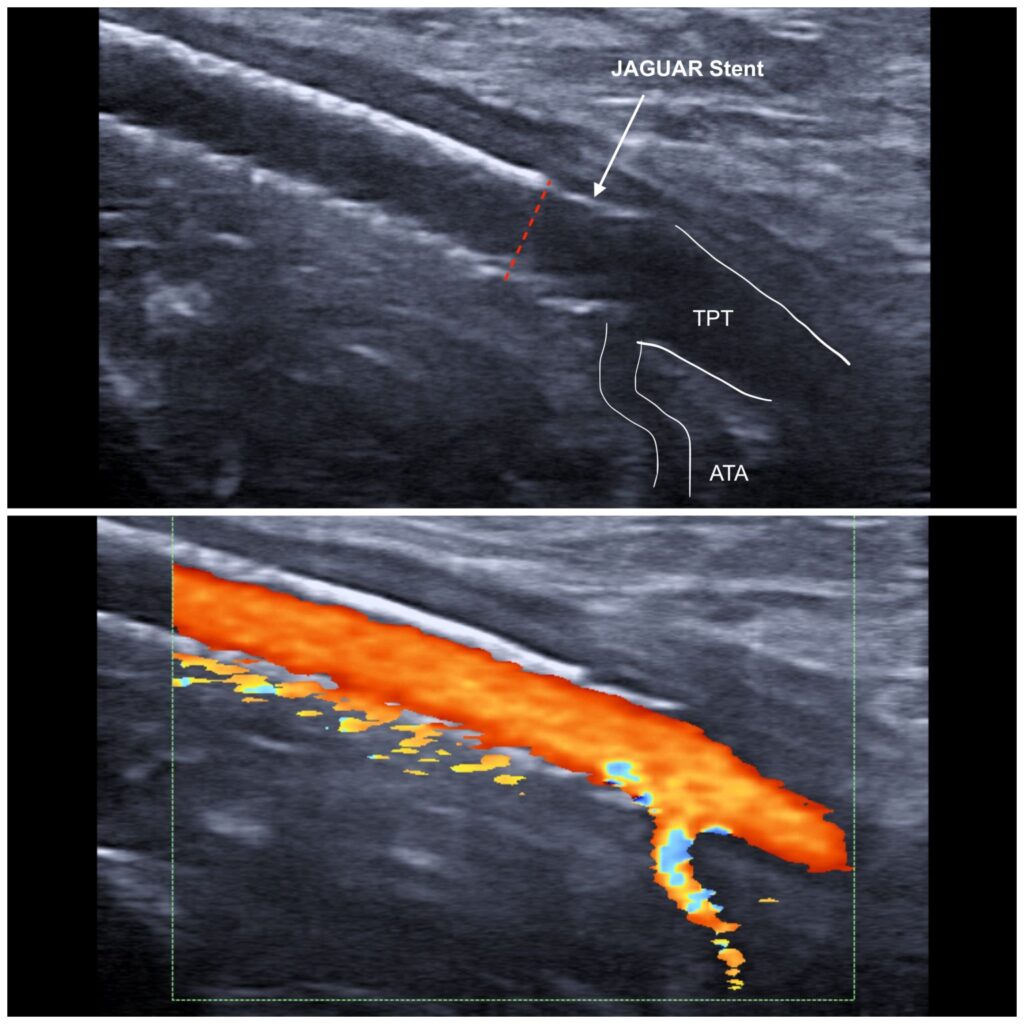

Seguimiento con eco-Doppler a 6 meses

- Implantación distal de stent JAGUAR (Balton – Grupo Logsa) en el segmento poplíteo distal, protegiendo la bifurcación tibial (arteria tibial anterior y tronco tibio-peroneo).

En el seguimiento a 6 meses mediante eco-Doppler, se confirma la permeabilidad del segmento tratado, con flujo adecuado hacia las arterias tibiales. Desde el punto de vista clínico, el paciente: